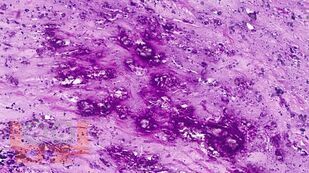

Учебное пособие разработано по дисциплине «Патологическая анатомия - патологическая анатомия головы и шеи» в соответствии с Федеральным государственным образовательным стандартом высшего профессионального образования для студентов, обучающихся по основным образовательным программам высшего образования - программам специалитета по специальности «Стоматология».

В учебном пособии представлен теоретический материал, перечень макропрепаратов и микропрепаратов, демонстрирующих типовые проявления патологических процессов. В цветных иллюстрациях и в описании микропрепаратов сделан акцент на наиболее важных гистологических изменениях, позволяющих на светооптическом уровне диагностировать и дифференцировать состояния, отклоняющиеся от нормы, в том числе с использованием различных гистологических окрасок. Пособие помогает выделить главные аспекты изучаемых патологических процессов, организовать и конкретизировать учебный процесс.